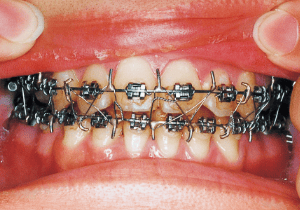

A case of diverted and cross bite during the deciduous dentition. Despite early treatment, the deviation progressively worsened with age, necessitating surgical treatment. At the initial visit, the patient had a deciduous dentition, and observation was planned (3). With the eruption of the permanent incisors, the mandible shifted slightly to the right, resulting in a cross bite (1) At this point, asymmetry can be confirmed in the front view. However, it is slight. The cephalometric X-ray reveals a structure with a slightly dominant mandible, but asymmetry in the mandibular ramus is not observed.

On the lateral cephalometric radiograph, the vertical height of the face appears greater than its depth. The lower facial height is also high, suggesting a shape somewhat prone to developing a protruding lower bite, though this does not raise significant concern (6). The facial photograph of front view shows slight asymmetry in the face, but it is not particularly extreme (1). The first phase of treatment corrected the anterior cross bite and deviation, but subsequent growth exacerbated the mandibular deviation, necessitating surgical treatment.

The Edgewise appliance was applied locally (8) and removed after 11 months (9). However, as the maxillary molar region gradually became crossbite, the maxillary arch was laterally expanded using a quad helix.

Although early treatment improved the slight deviation observed during the deciduous dentition stage, it became apparent that the deviation increased with age, eventually exceeding the limits of treatment. This appears to be an innate deviation, and the developmental pattern observed in this case seems to disregard the occlusion. Four first premolars were extracted (15), crowding was corrected and space closure was performed (16), and surgical intervention improved the deviation (17).